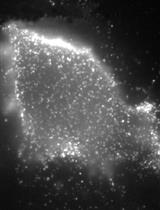

Intracellular Staining for Phosphorylated STAT4 and STAT5 in Mouse Splenocytes

Cover of PLOS Pathogens, featuring study using the protocol.